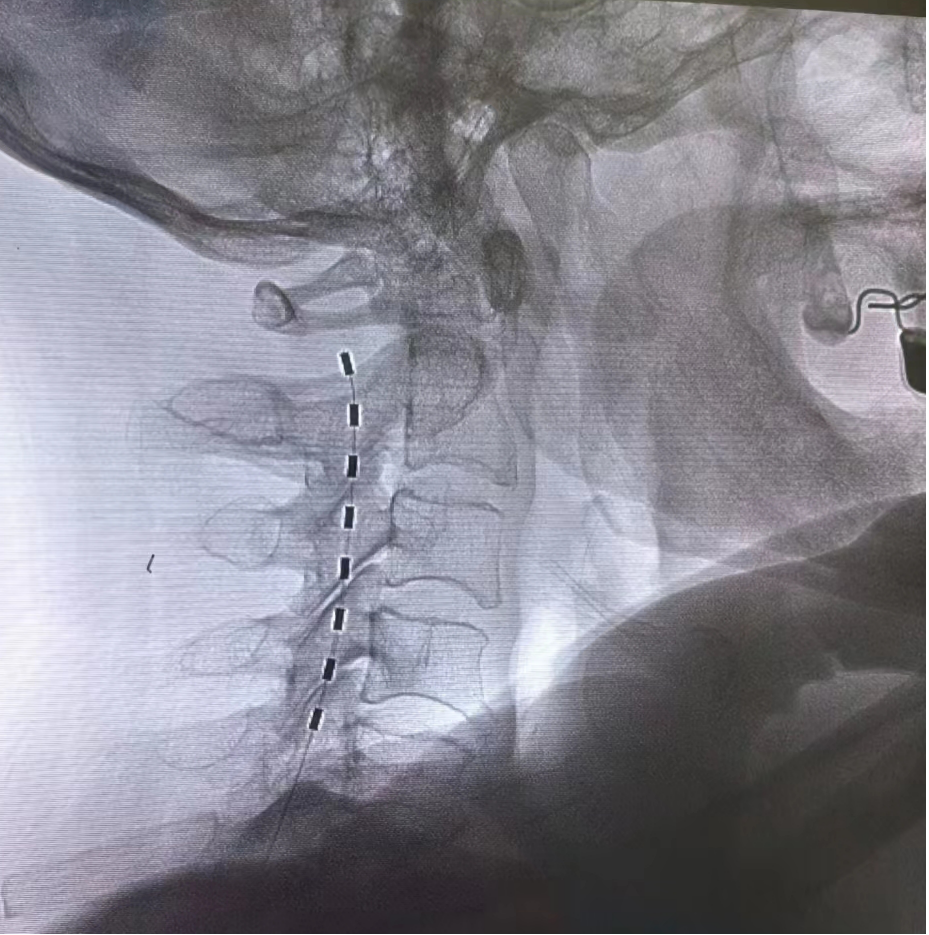

神經(jīng)調(diào)控:包括神經(jīng)射頻、電刺激等,是目前治療帶狀皰疹后神經(jīng)痛最有利的手段。通過(guò)干預(yù)神經(jīng)電信號(hào),減少疼痛傳遞,促進(jìn)鎮(zhèn)痛物質(zhì)釋放,可以達(dá)到更佳持久的鎮(zhèn)痛效果。尤其適用于后遺神經(jīng)痛的治療。